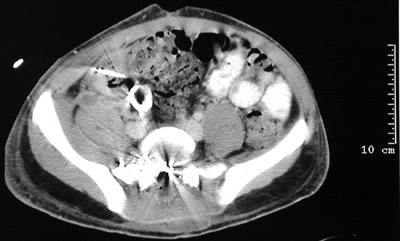

| The pelvic CT scan views above demonstrate a gunshot wound to the spine with bright bullet fragments and bone. A neurosurgical procedure was necessary to remove fragments from the spinal canal. In the view below, the density of the metal bullet scatters the x-rays ("beam hardening" artefact). |